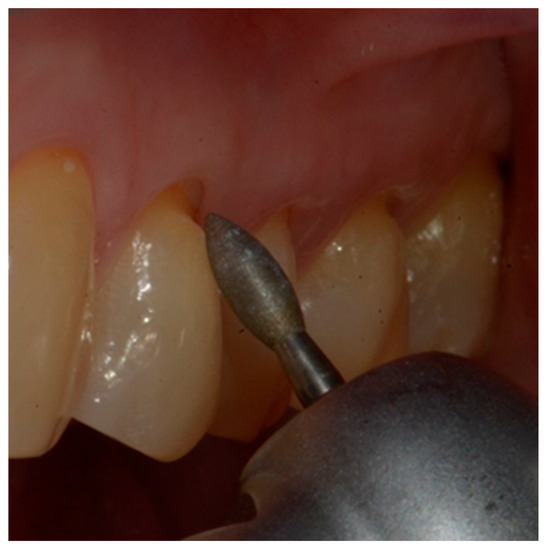

- Finishing the restoration with a coarse- (80 μm) and a fine- (50 μm) grain flame bur placed on the most apical point of the restoration, without touching the dental tissue with the tip, in order to create an angle of approximately 45° and maintain a convex profile (Figure 8).